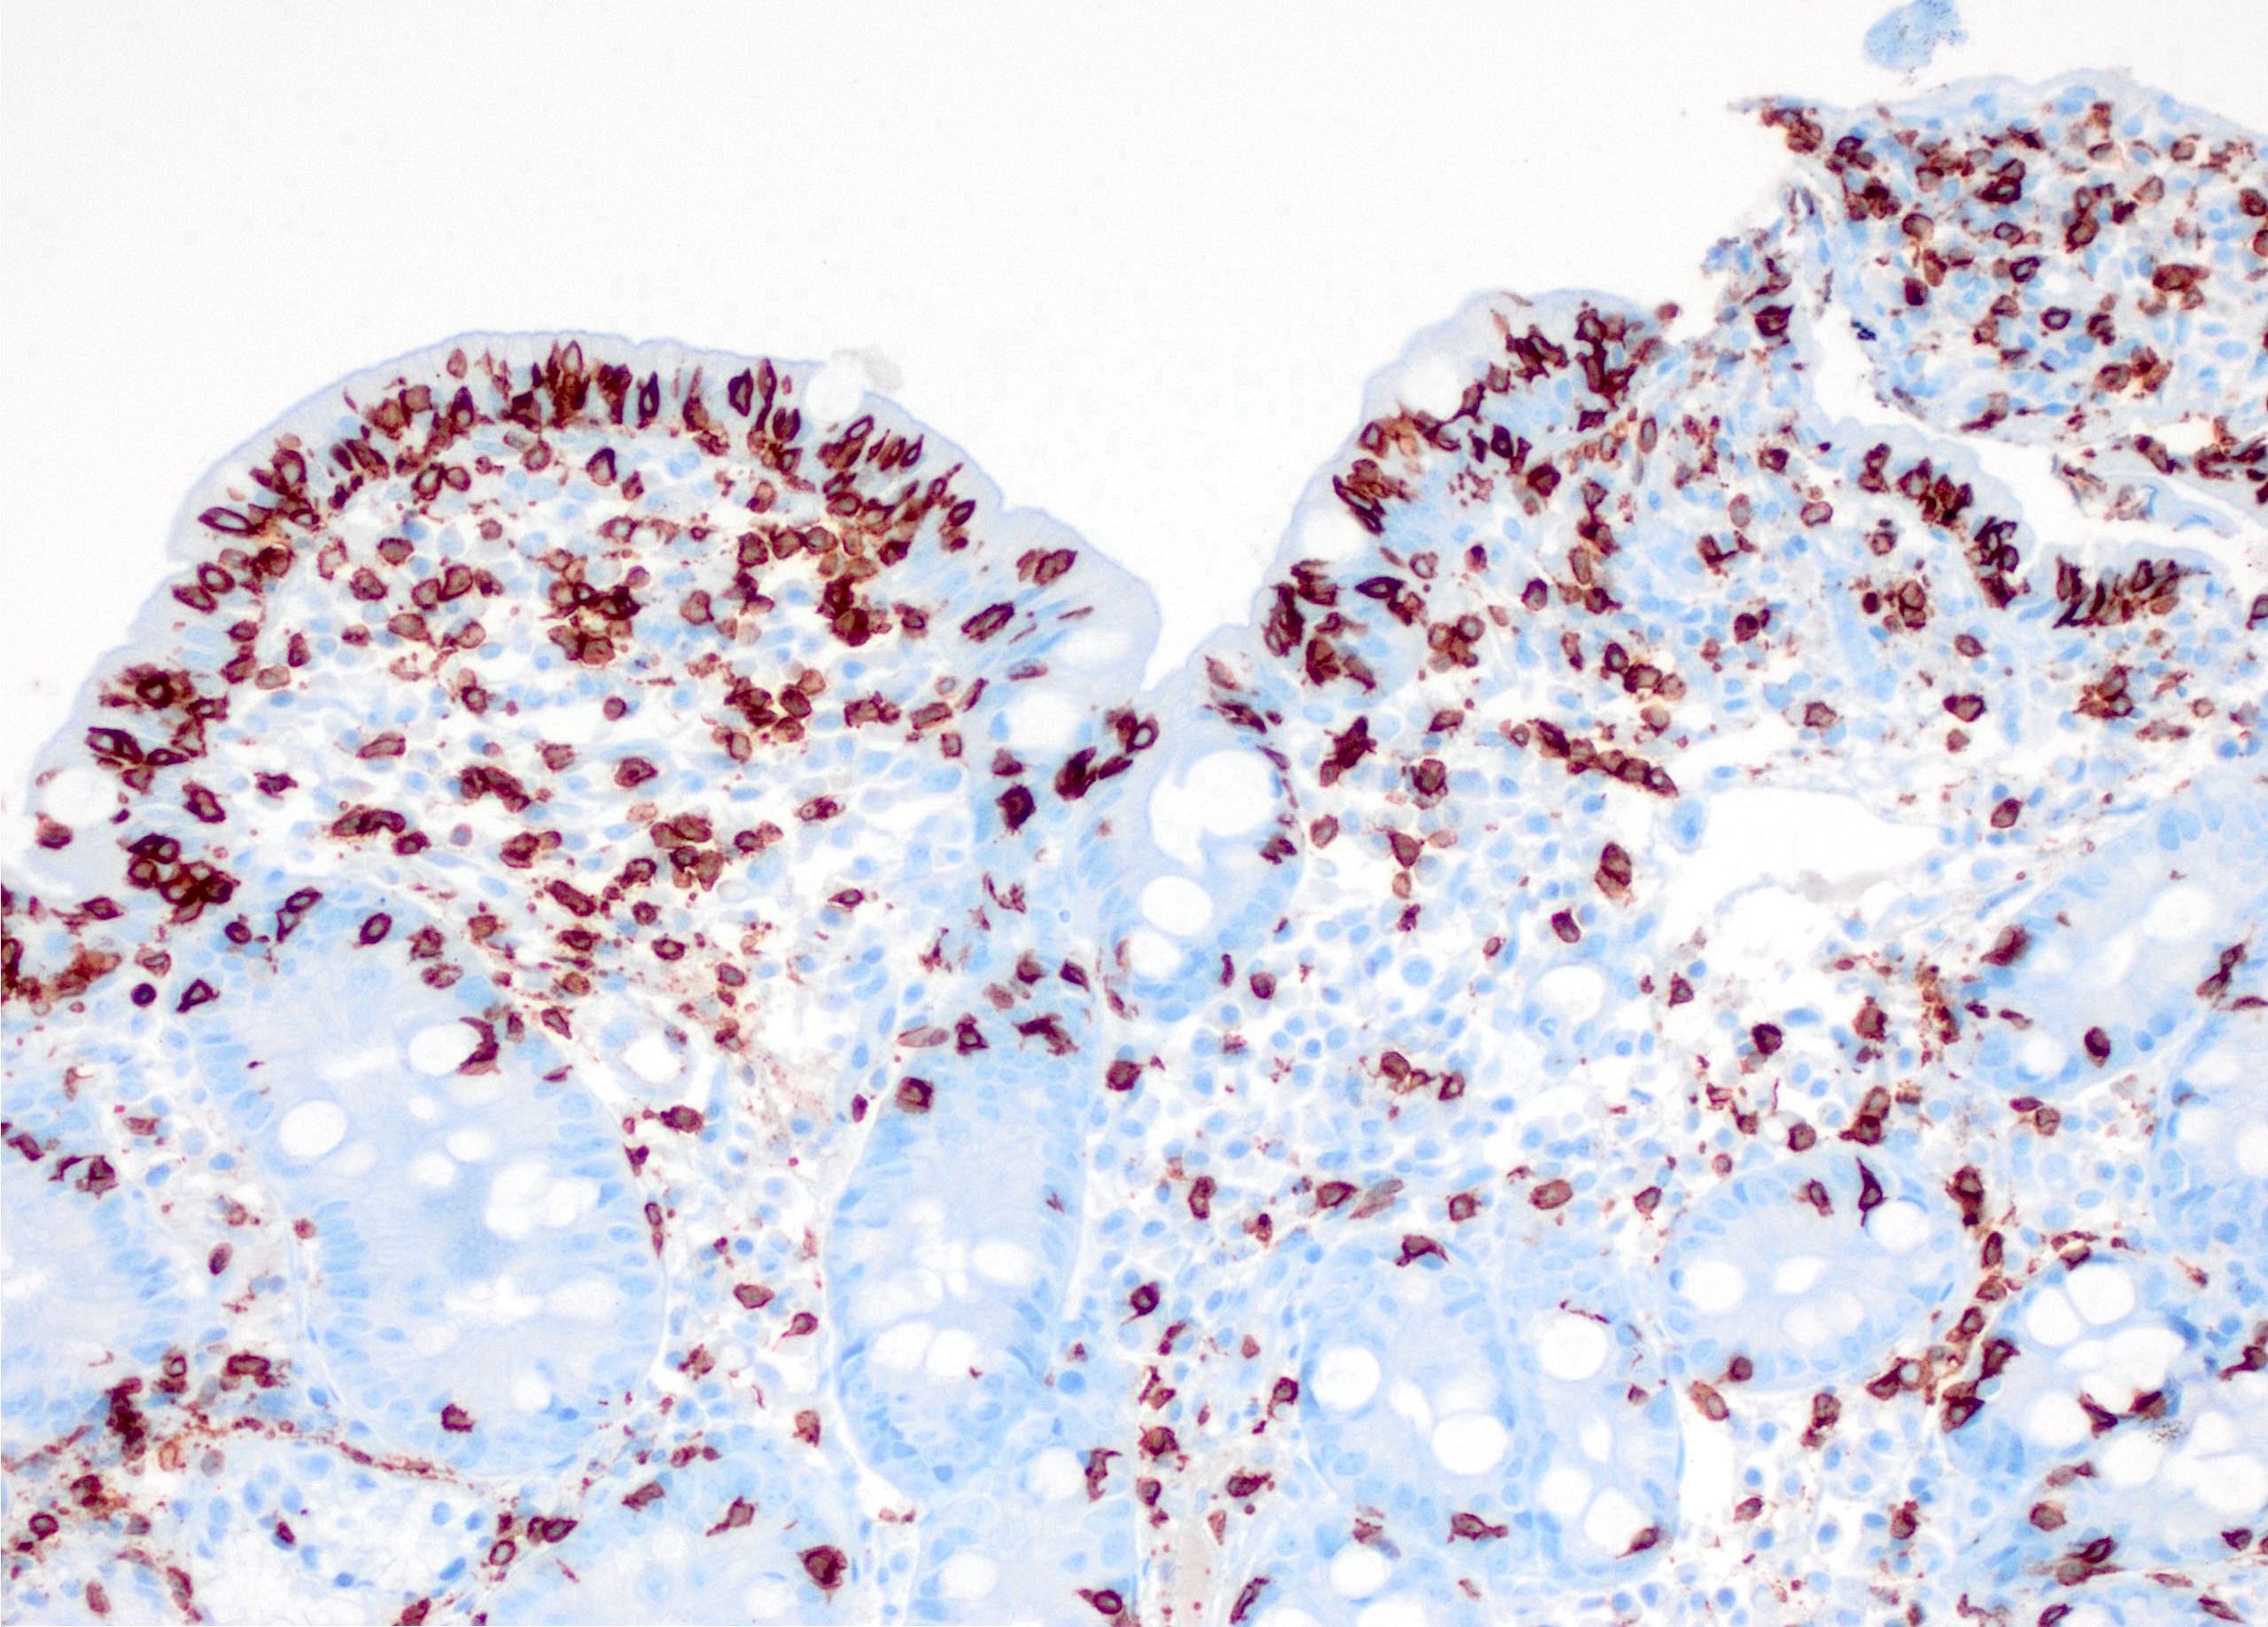

- Refractory celiac disease type 2 is characterized by loss of multiple surface T cell markers like CD3, CD7 and CD8 in more than 20% of the intraepithelial lymphocytes on flow cytometry

- Flow cytometry: quantification of intraepithelial lymphocytes by flow cytometry (called IEL lymphogram), demonstrates that the IELs are antigen experienced T lymphocytes and bear the αβ (> 90%) and γδ (< 10%) receptors

- In celiac disease, the total IELs are increased, along with a permanent increase in γδ IELs and a decrease in CD3 IELs (Auto Immun Highlights 2016;7:14)

Microscopic (histologic) description

- Histological elementary lesions (Dig Liver Dis 2011;43:S385, Semin Diagn Pathol 2014;31:124):

- Increased intraepithelial T lymphocytes (IEL):

- 25 - 29 IEL/100 enterocytes is considered borderline

- > 30 IEL/100 enterocytes represents a pathological lymphocytosis

- Increased intraepithelial T lymphocytes (IEL):

Microscopic (histologic) images